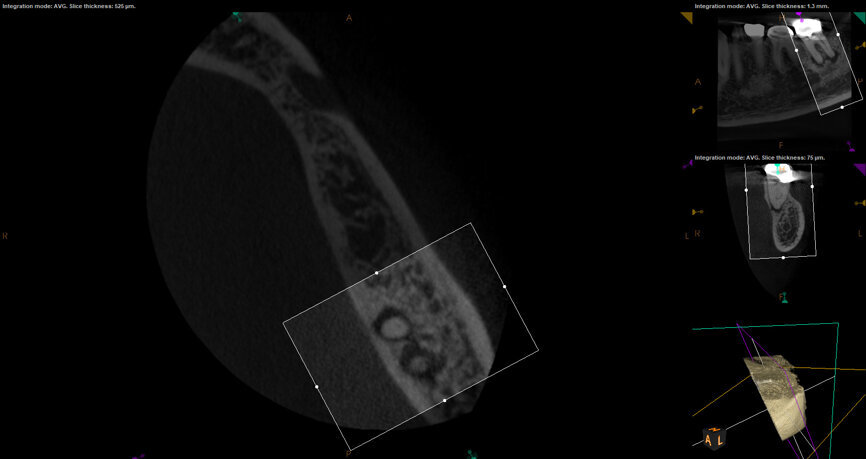

Fig. 17a: Case assisted with CBCT to determine anatomy pre-operatively. Note the multiple cross sections moving apically and the correlation to the 2-D view. Note also the conservative taper in relation to the root width. (Courtesy of Dr. Brett Gilbert)

Fig. 17b: Case assisted with CBCT to determine anatomy pre-operatively. Note the multiple cross sections moving apically and the correlation to the 2-D view. Note also the conservative taper in relation to the root width. (Courtesy of Dr. Brett Gilbert)

Fig. 17c: Case assisted with CBCT to determine anatomy pre-operatively. Note the multiple cross sections moving apically and the correlation to the 2-D view. Note also the conservative taper in relation to the root width. (Courtesy of Dr. Brett Gilbert)

Fig. 17d: Case assisted with CBCT to determine anatomy pre-operatively. Note the multiple cross sections moving apically and the correlation to the 2-D view. Note also the conservative taper in relation to the root width. (Courtesy of Dr. Brett Gilbert)

Fig. 17e: Case assisted with CBCT to determine anatomy pre-operatively. Note the multiple cross sections moving apically and the correlation to the 2-D view. Note also the conservative taper in relation to the root width. (Courtesy of Dr. Brett Gilbert)

Fig. 17f: Case assisted with CBCT to determine anatomy pre-operatively. Note the multiple cross sections moving apically and the correlation to the 2-D view. Note also the conservative taper in relation to the root width. (Courtesy of Dr. Brett Gilbert)

Managing complex anatomy is much simpler if the clinician has a pre-operative road map. The CBCT provides the roadmap and the surgical microscope the lens (literally) through which to visualize the result. Aside from a relaxed patient who is profoundly numb, being able to visualize anatomy by taking a pre-operative (and possibly intra-operative) CBCT and using a surgical microscope during treatment have no substitutes. They are the current “Gold Standard” in that 3-D imaging shows the clinician the true reality of a clinical situation as opposed to the suggestion gained from a 2-D radiograph. Proper interpretation of imaging prior to and/or during endodontic treatment goes a long way in taking the “guesswork” out of identifying canal location and other anatomical complexities as the procedure unfolds. In a 2014 study by El Fayad and Johnson, it was determined that when having a pre-operative CBCT as compared to 2-D radiographs alone, the treatment plan was modified 62 percent of the time. This is a huge game changer to think that the information learned from 3-D imaging changed the plan of treatment over six times out of 10 (Fig. 4).[2]